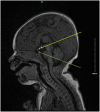

Congenital panhypopituitarism unmasked by PHACE screening